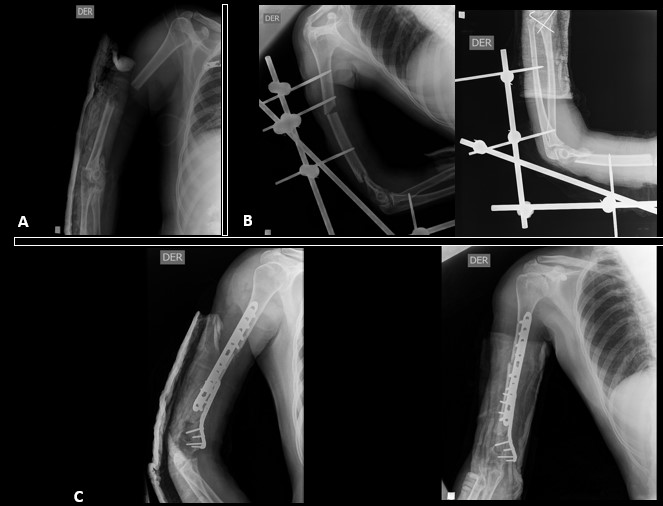

The definitive stabilization of long bone fractures in the first 24 hours positively impacts survival1,21-23. Hemodynamically stable patients should undergo definitive fixation of fractures during the first surgery (Figura 3). However, prolonged interventions (over 90 minutes) in hemodynamically unstable patients are associated with unfavorable outcomes. Furthermore, major surgery can trigger and increase immune response resulting in a clinical condition called “Second Trauma” 15,17,24. Therefore, delayed definitive stabilization has been implemented in hemodynamically unstable patients to reduce the effect of the second trauma 25,26. These patients should undergo damage control with a temporary fixation, followed by physiologic stabilization and a deferred definitive fixation in a second surgical time 5 to 10 days after damage control (Figura 4) 10,16,27,28.